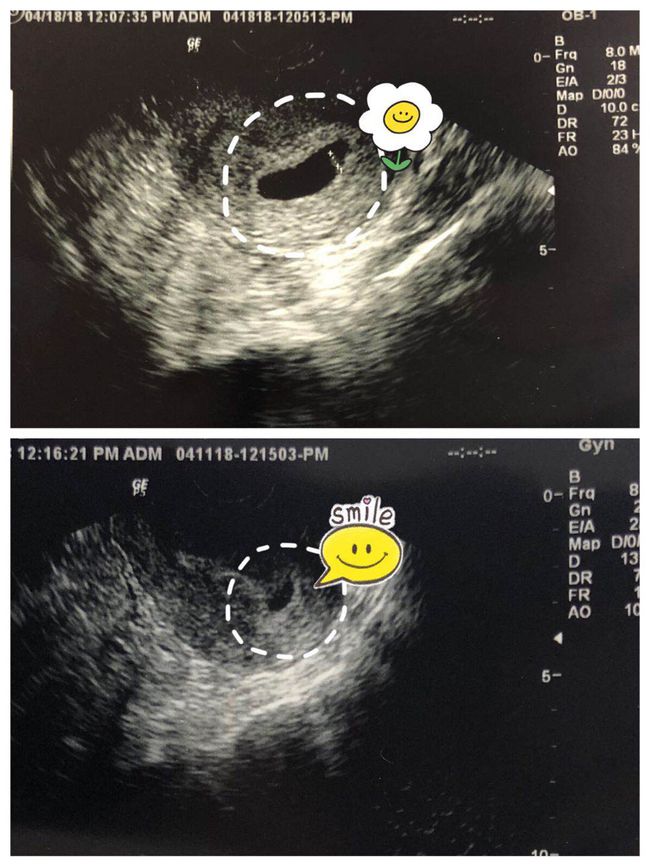

虽然顺产分娩是一个自然的过程,但它的过程却充满了艰辛和挑战。以下是一些实拍顺产分娩过程的片段,让我们一起来感受一下这个过程的艰辛。

这是第一产程的实拍画面,我们可以看到母亲在宫缩的疼痛中努力地呼吸,她的表情充满了痛苦和坚持。